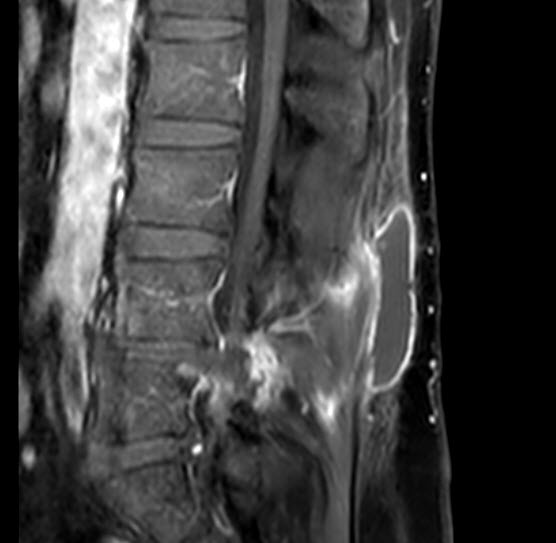

09-MARCH-2020  HUSNI LUTFI ABDEL-HAQ  45 YEARS  POST-TRAUMATIC CSF LEAK FORM THE PREVIOUSLY OPERATED DISCECTOMY L4-5.

The patient was operated by me for huge extruded disc L4-5 with left downward migration 15-November-2018. The patient then came 09-December-2019 still complaining of left sciatica with improvement of the power of the left foot. MRI performed 07-December-2019 showing small piece of disc fragment at L4-5 left side. Dorsiflexion of the left foot at that time was +4/5. The patient then came 27-February-2020 telling that he got severe headache with fainting for 15 days several days after falling down 10-February-2020. The patient then noticed a pocket of CSF collection under the skin at the operative site and above 2 days later. Routine MRI done 18-February-2020 showing CSF pocket at the level of the operative site.

The patient was sent for MRI of the lumbar spine with 3D myelography to confirm the presence of the CSF leak and its origin. It was performed 08-March-2020 and showed that the defect was in the upper left corner of the previously exposed dura.

CSF leak usually take place the first week after surgery. In the case the patient suffered trauma after 2 years of his surgery. The dura usually is hard to be torn directly at the surgical field. It must be torn around the scar tissue. for what 3D myelography was performed. According to its data it must be from the left upper corner of the dural scar.

During surgery, the findings were different. The scar was longitudinally torn at the midline and inferior.

Fig:-1 The CSF pocket.